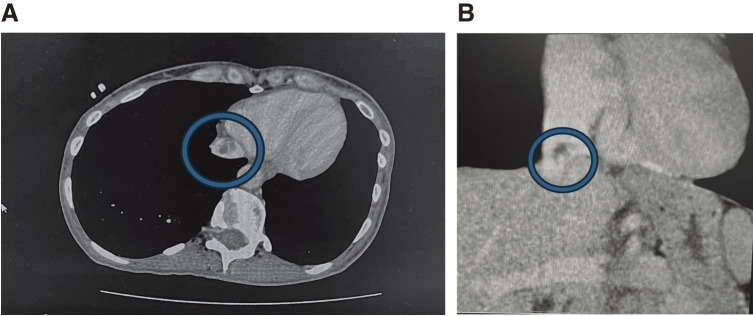

We experienced a case in which a myxoma in the inferior vena cava (IVC) was surgically removed along with the IVC using deep hypothermic circulatory arrest. A 42-year-old female with no subjective symptoms was incidentally found to have a mass in the IVC at the junction of the hepatic veins on contrast-enhanced computed tomography. Ultrasonography revealed a mobile tumor attached to the junction of the hepatic veins. Surgery was performed via median sternotomy and laparotomy. Cardiopulmonary bypass and deep hypothermic circulatory arrest were utilized to safely operate.